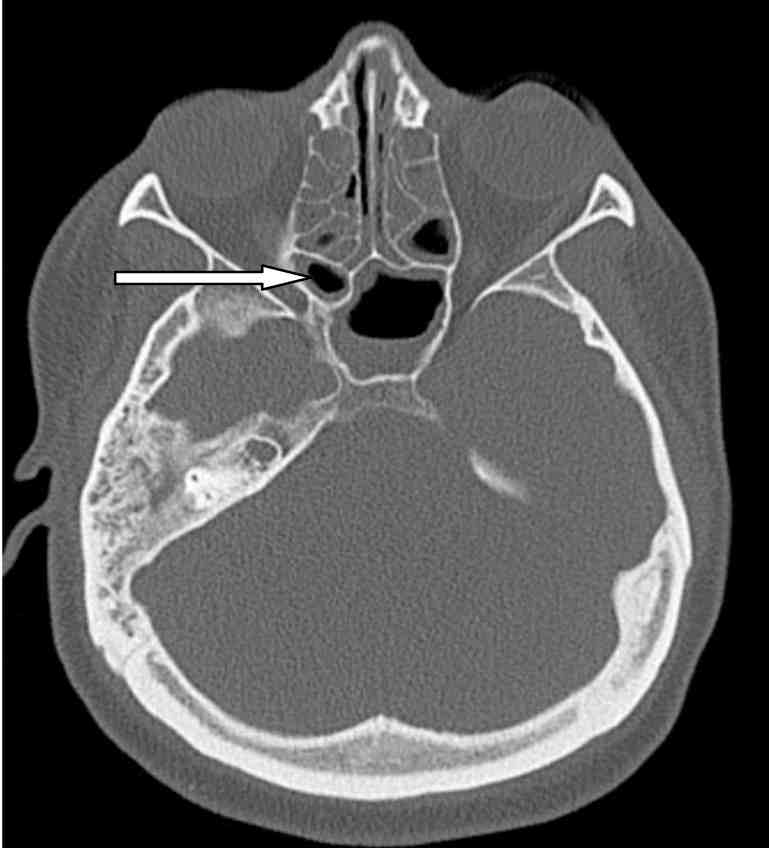

Endoscopic sinus surgical procedure signs, risks & headaches. Study sinus surgical treatment recuperation time, risks, complications, what to expect before, at some stage in, and after sinus surgery. While to name the doctor of any postsurgery. Endoscopic sinus surgical procedure american rhinologic. Endoscopic sinus surgery. Marc dubin, md jivianne lee, md troy d woodard, md sarah k clever, md advent sinus surgical treatment has genuinely evolved over the years. Sinus sickness & surgery offerings * joliet, morris il. Frequently asked questions what is sinusitis? Sinusitis is an inflammation of the sinus lining normally due to bacterial, viral, and / or microbial infections; as. Sinus surgery india hospital tour. Sinus surgical operation india, sinus surgical procedure overseas in india gives information on value sinus surgery india,sinus surgery hospitals india,sinus ent surgeons india,sinoscopy sinus india. Sinus surgical operation headaches sinus surgical treatment headaches. Search for sinus surgical procedure complications with 100's of outcomes at webcrawler. Complications of sinus surgical procedure american rhinologic. Headaches of sinus surgical procedure. Joseph han, md jay m. Dutton, md, facs introduction surgery of the nasal hollow space or its adjacent paranasal sinuses is normally. Headaches of sinus surgery american rhinologic. Headaches of sinus surgery. Joseph han, md jay m. Dutton, md, facs advent surgical operation of the nasal cavity or its adjoining paranasal sinuses is commonly. Dehiscence of the lamina papyracea of the ethmoid bone ct. Dehiscence of the lamina papyracea of the ethmoid bone ct findings man moulin,1 patrick dessi,2 christophe chagnaud,1 jeanmichel bartoli,1 paul vignoli,1 jeanyves.